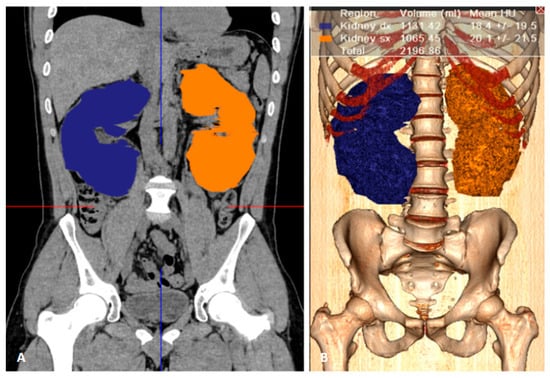

2.3. Manual Segmentation

2.4. Ellipsoid Formula